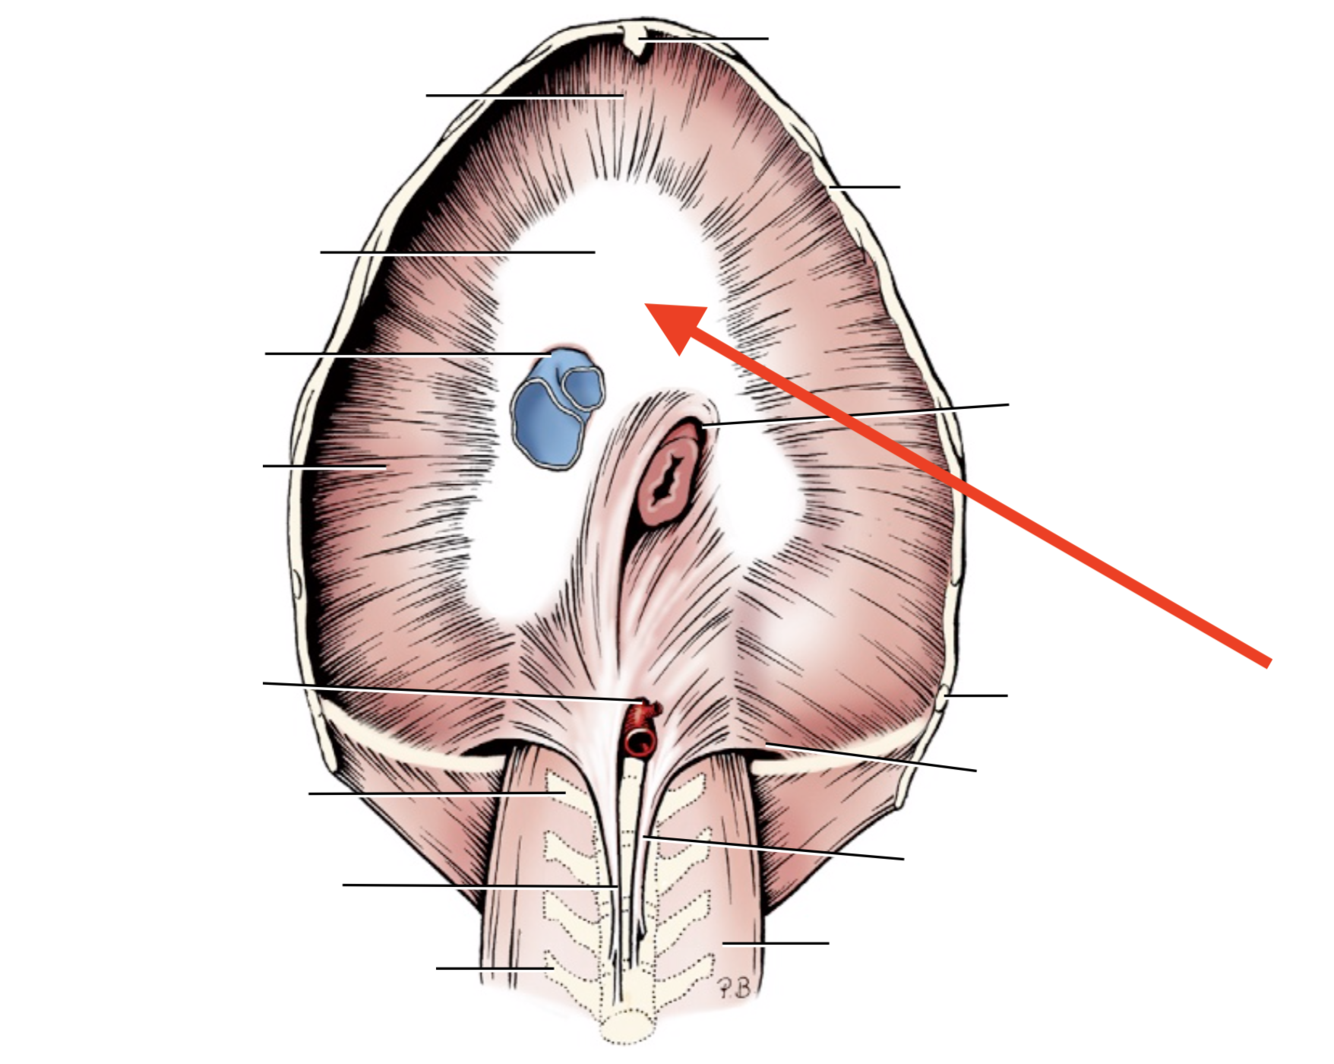

Name given to the most cranial part of the diaphragm.

Cupula Diaphragmatis

Q

Pars sternalis

Q

Foramen vena cavae

Q

Pars costalis

Q

Hiatus aorticus

Q

Arcus lumbocostalis

Q

Hiatus oesophagus

Q

Crus sinistrum

Q

Crus dextrum

Q

Centrum tendineum

Q

Corona muscularis